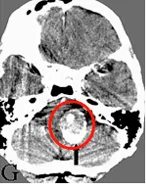

40多岁日本男性,出现轻微头疼并持续2天,但并无任何其他神经系统缺陷,CTA显示双侧VADA并蛛网膜下腔出血(图3a)。随后入院进行第一次手术,Kawashima(川岛明次)教授通过左侧枕下外侧入路手术成功夹断左侧破裂的VADA(图3b),小脑后下动脉(PICA)未参与VADA,无任何术中并发症。

图3a:术前CTA显示双侧椎夹层动脉瘤(箭头)。

图3b:术后3天CTA显示左侧VADA切除(箭头)。